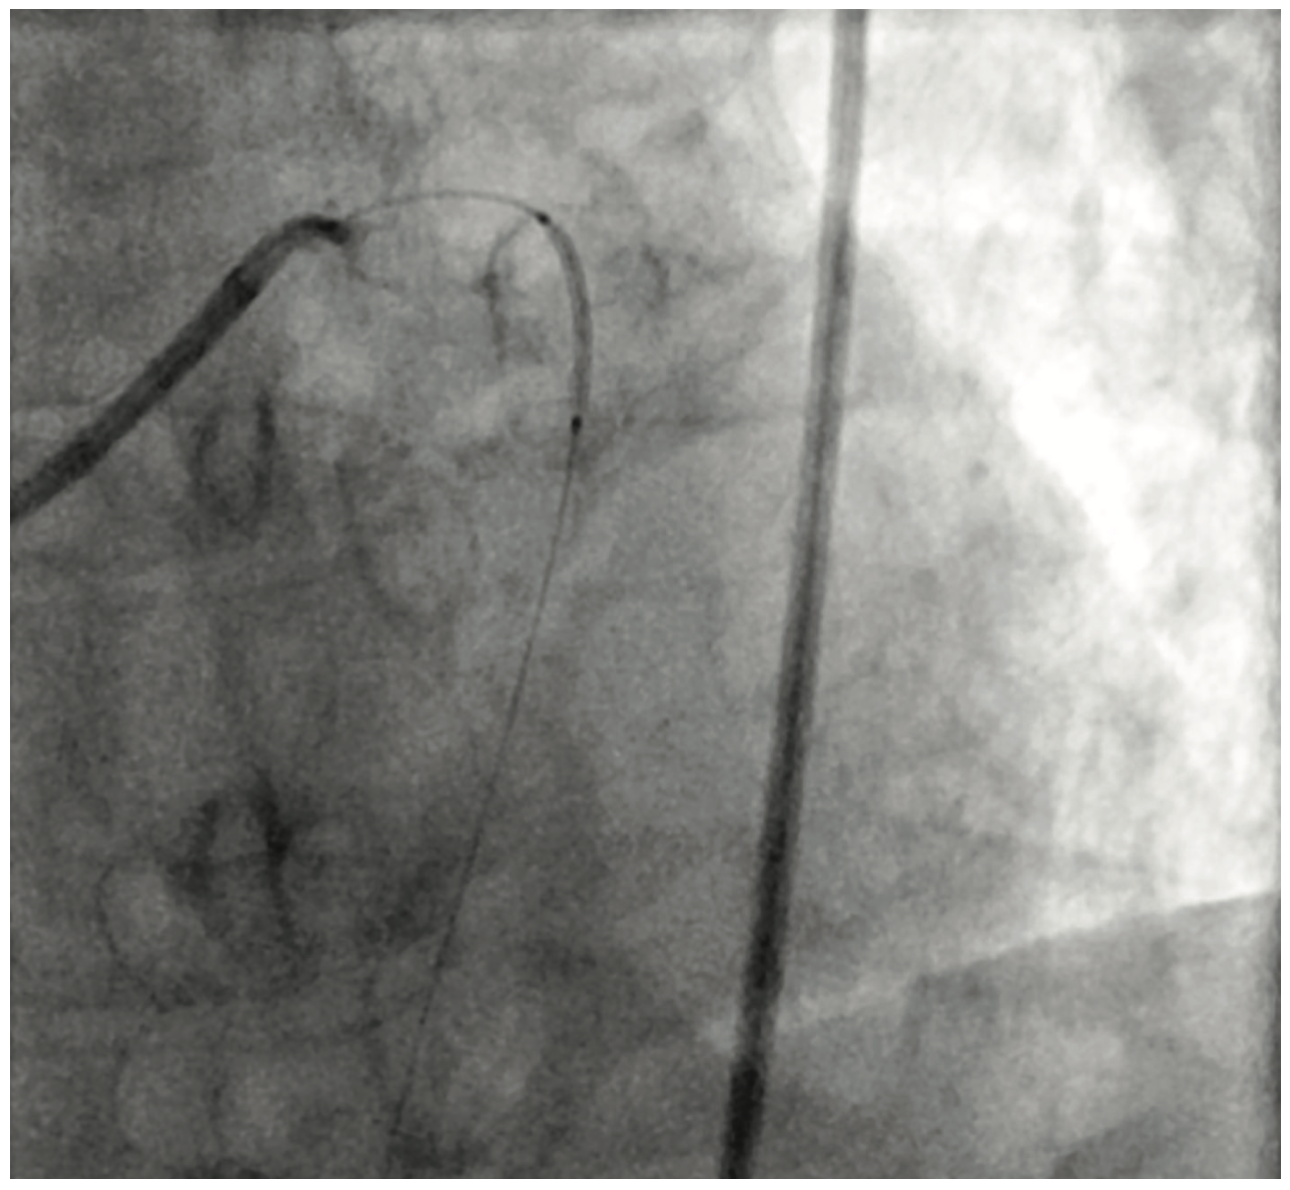

Figure 1. Occluded proximal LAD.

Cardiac catheterization showed total occlusion of the left anterior descending artery (LAD) with multiple coronary aneurysms in the LAD, left circumflex (LCx), and right coronary arteries. There was TIMI 0-1 slow flow within the coronary aneurysms. An eptifibatide bolus and drip was started. Aspiration thrombectomy using an Export catheter (Medtronic) and then rheolytic thrombectomy using an AngioJet catheter was performed on the proximal and mid LAD. A 4.0 x 16 mm bare metal stent was placed. However, the patient became hypotensive in the cath lab and a balloon pump was inserted. Prior to leaving the lab, there was resolution of the ST segment elevations. The patient was started on both a heparin drip and low-dose dopamine drip.